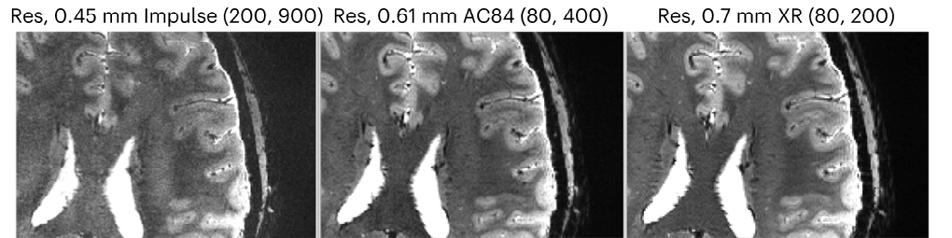

Next Gen 7T MRI Allows Neuroimaging with Unprecedented Precision

Conventional MRI scanners for clinical use generate images using magnets whose strength is measured at 1.5 Tesla (T) or 3T. At a limited number of locations across the world, clinicians and researchers have access to MRI scanners with much more powerful magnets operating at 7T. With the several dozen 7T machines located in the United States, imaging scientists can gain much higher resolution images, examining the tiny details that make up the architecture of the brain and body. However, there is still a ceiling to that resolution, as even with the most optimal scan parameters, features smaller than one to two millimeters vanish into the abstraction of the voxel, a three-dimensional pixel.

In December 2023, an international team of scientists including UCSF faculty member An (Joseph) Vu, PhD, broke that ceiling. Led by UC Berkeley professor and president of Advanced MRI Technologies, David Feinberg, PhD, MD, the team is a multi-institution collaboration with scientists from UCSF including Drs. An (Joseph) Vu and Pratik Mukherjee, UC Berkeley, Harvard, Siemens Healthineers (Erlangen, Germany), Advanced MRI Technologies (Sebastopol, CA), and MR CoilTech LTD (Glasgow, UK). Together, they constructed a next generation ultra-high resolution 7T MRI scanner, which achieves up to 10-fold increase in resolution over the current 7T standard, which is 50 times more detail than the hospital standard 3T scanners. With this new tool, functional images can now be captured with a voxel size of less than half a millimeter. This allows scientists to, for the first time, image functional clusters of neurons across

the entire brain, organized in cortical cell layers and cortical columns, opening up the study of a new realm of meso-scale local neurocircuitry.

Thanks to additional funding obtained by Drs. Vu, Feinberg, and Alexander Beckett, the NexGen 7T is now available to scientists across the Weill Neurohub consortium of UCSF, UC Berkeley, and the University of Washington, and as an international resource through the NIH BRAIN Initiative. The NexGen 7T MRI scanner is described in a Nature Methods article “Next-generation MRI scanner designed for ultra-high-resolution human brain imaging at 7 Tesla.”1

Although the NexGen 7T is not yet FDA approved, it has achieved remarkable breakthroughs in fast, high-resolution neuroimaging by virtue of several key advancements: an extremely powerful head gradient system, the first 128 channel receiver systems integrated into a 7T scanner, and several universally optimized RF pulse sequence protocol.

The new head-only magnetic gradient coil design that is an order of magnitude more powerful than those in

NexGen 7T 0.6 mm isotropic diffusion images (b=0 s/mm2) depicting fine anatomical structures including hippocampal layers and perivascular spaces.

commercially available 7T scanners. This advancement in gradient performance was achieved with a novel 3-layer wire winding design instead of only two layers. The faster and stronger the magnetic gradients are, the faster the MRI data can be encoded, fighting the clock of T2 signal decay and blurring. There were a lot of physics challenges to achieve such strong and fast gradients. In addition to the need to minimize peripheral nerve stimulation effects, the mechanical forces interacting with the field and the sound pressure levels both increase as the main magnetic field gets stronger. These challenges were detailed in “Acoustic noise reduction in the NexGen 7 T scanner.”2 For all these reasons, the scanner needed to be designed at a system-wide level, factoring in RF coil design, gradient coil design, and magnet design.

Another breakthrough came via the development of 64 channel and 96 channel receiver arrays coupled with the 128-channel receiver system, vastly improving on the standard 32 channel system in terms of SNR and the ability to accelerete the imaging. As the number of receiver channels increases, the size of the individual coil loops in the head coils become smaller, which in turn provides higher sensitivity and improved ability to accelerate data acquisition for fast, ultra-high resolution functional and structural MRI.

The improvements are not only related to hardware, as RF pulse sequence design has played a great role in these milestone achievements. In collaboration with Dr. Nicolas Boulant (CEA, NeuroSpin, France), the team has implemented precisely pre-calibrated universal pulses which can produce structural images of exquisite quality on almost any subject you place inside the scanner without the need for lengthy pre-scans or subject-specific calibrations. Furthermore, in two collaborations with Dr. Renzo Huber (NIMH, NIH) and with Dr. Suhyung Park (Chonnam National University, S. Korea), improvements in functional imaging pulse sequences more precisely identify neuronal activity in cortical layers, and similar resolution gains in collaboration by achieving unprecedented isotropic resolution in the 0.35mm – 0.6mm range.